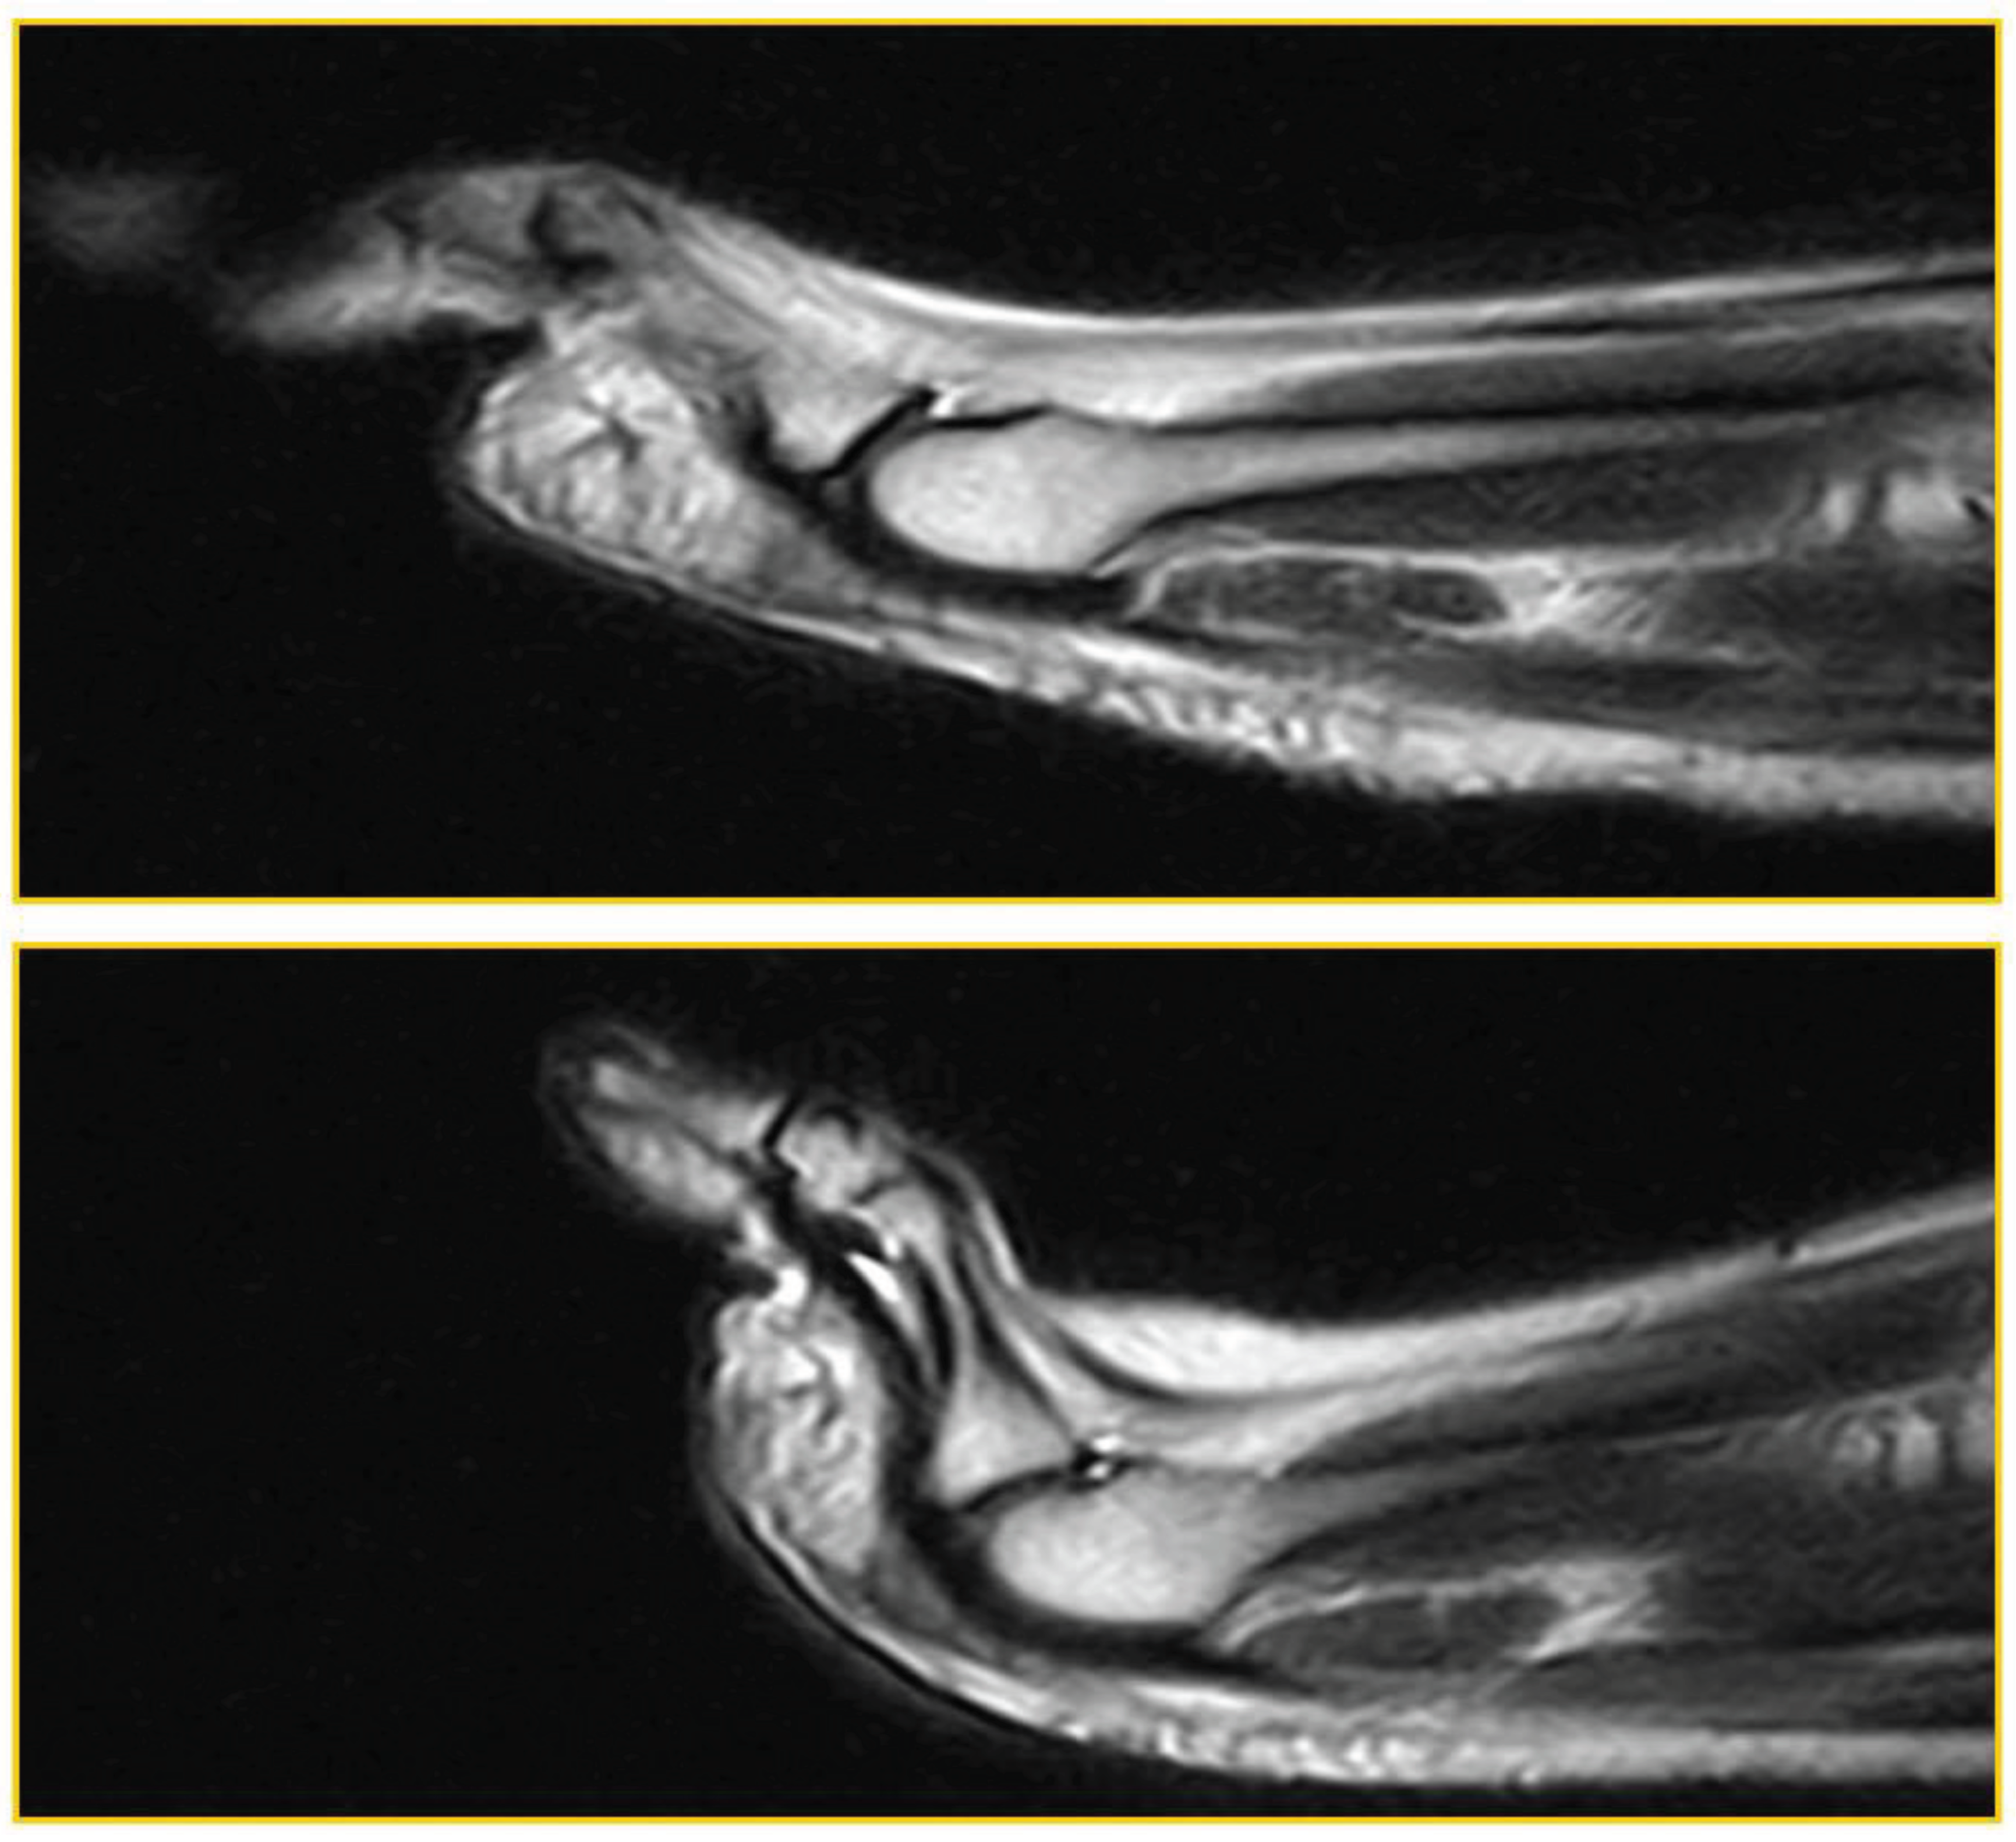

Patient 5: symptomatic (59 years, woman). False negative: Joint instability; dorsal subluxation of the proximal phalanx, visible only during ST, in the absence of PP tear (Figure 6).

Patient 6: symptomatic (54 years,man). False negative: negative for PP lesion in standard position. The lesion becomes evident during ST (Figure 7).

The plantar plate lesion, evident only with the stress test, affects the plantar plate at the insertion on the proximal phalanx, on the deep side.

Figure 6. False negative (instability).

Figure 7. False negative.